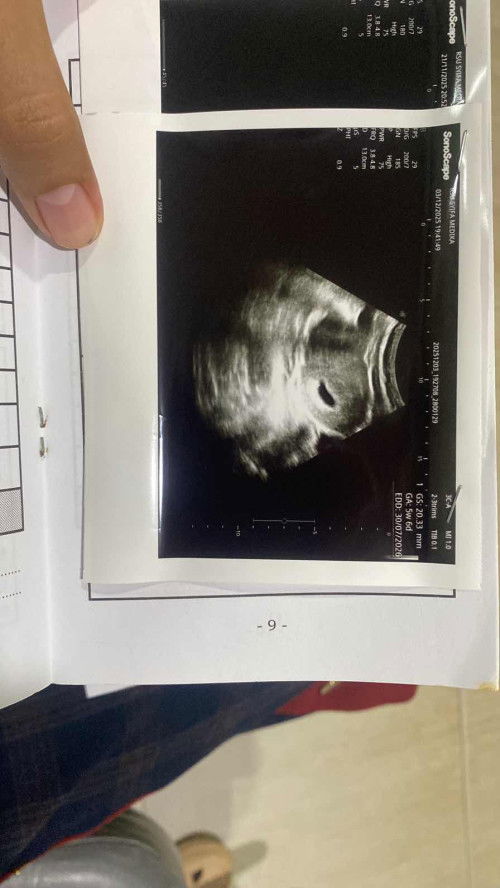

Usg 5week6day

Bun usg kehamilan usia 5minggu6hari segini kantongnya, tapi belum keliatan janinnya , nanti disuruh balik lagi 22 des, ada yg sama kan ya disini usia 5week masih berupa kantong bun ? Soalnya di bbrp kehamilan 5week ada yg udh keliatan janinnya , Tpi usg pertama di 4w dan tdi mlm di usia 5w6d itu udh jauh berkembang bngt kt dokter nya, dan hal yg wajar klo blm ada janin #5minggu6hari #bantujawab #firstmom #sharing #Usg